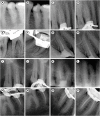

Objectives: This study aimed to investigate the efficacy of ionic and non-ionic-based contrast media (in vitro study) and the combinatorial effect of chitosan-based endo-radiopaque solution (CERS) (in vivo study) for visualization of the root canal anatomy.

Materials and methods: In vitro study (120 teeth): The root canal of maxillary premolars and molars (in vitro group 1 and 2 respectively, n = 60 each) were analyzed using 4 different contrast media (subgroups: Omnipaque 350, Iopamidol, Xenetix 350, and Urografin 76; n = 15 each) in combination with 5.25% sodium hypochlorite (NaOCl). Based on the results of the in vitro study, in vivo study (80 teeth) was done to compare Xenetix 350 + 5.25% NaOCl with CERS (in vivo group 1 and 2 respectively, n = 40 each) on maxillary and mandibular premolars and molars. Two endodontists used radiovisiography to assess the depth of ingress and identify the aberrant root anatomy after access cavity preparation, and after initial cleaning and shaping of canals. Kruskal-Wallis test was used for in vitro comparison (p < 0.05), and Wilcoxon signed-rank test and Mann-Whitney U test for in vivo analysis (p < 0.01).

Results: In vitro study, Xenetix 350 + 5.25% NaOCl facilitated a significant higher visualization (p < 0.05). For in vivo study, CERS had a statistically significant depth of ingress (p < 0.01), and was efficient in identifying the aberrant root canal anatomy of premolars and molars.

Conclusions: CERS facilitates better visualization of the root canal anatomy of human premolars and molars.